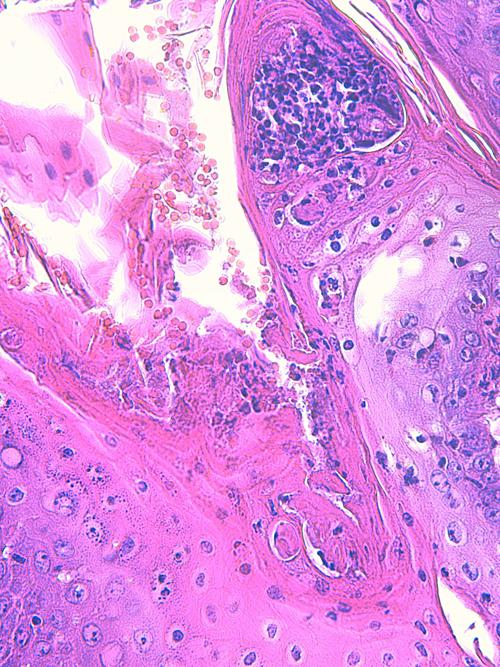

Photo 13 (Hémalun Eosine X 100) peau velue : dans le derme, de nombreux

follicules pileux sont rompus doannant naissance à des foyers furonculeux.

Légendes de la Photo 13 :

- Étoiles noires : infiltrat inflammatoire dermique et effondrant le follicule pileux

- Double flèche pointillée noire : gaine épithéliale externe du follicule pileux

- Ronds marrons : tige pilaire

- Flèches jaunes : rupture du follicule pileux (furonculose)

Photo 14 (Hémalun Eosine X 100) peau velue : Dans le derme, les pelotons de

glandes sudorales épitrichiales sont entourés de manchons inflammatoires

associant principalement granulocytes éosinophiles et plasmocytes.

Légendes de la Photo 14 :

- Étoiles rouges : lumière des glandes sudorales apocrines épitrichiales

- Flèches jaunes : infiltrat inflammatoire dermique en manchons péri-sudoraux